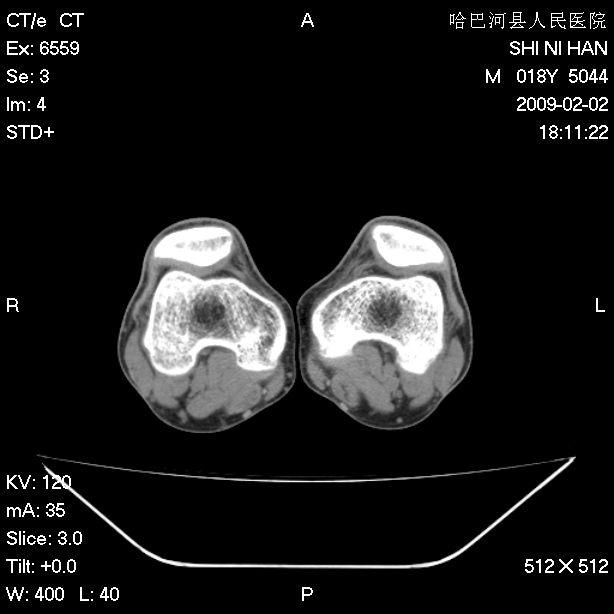

标题: CT17889:外伤后右膝关节反复疼痛3年余 [打印本页]

标题: CT17889:外伤后右膝关节反复疼痛3年余

mri检查,看看半月板情况如何。

可能韧带有问题!

ct未见明显异常。关节腔未见明显积液,半月板未见明显撕裂。但最好还是mri看看韧带及半月板情况。